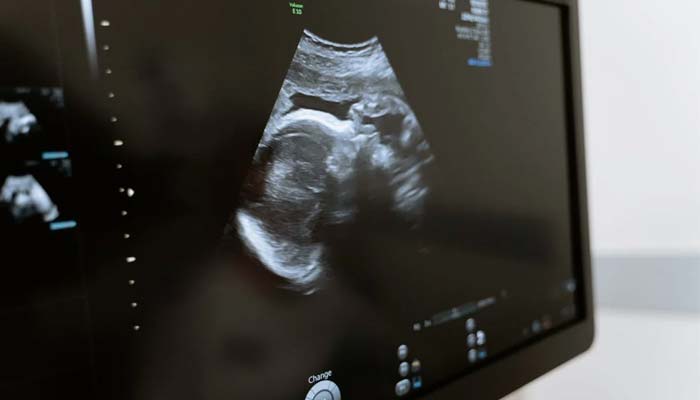

More than half of US women who received a uterus through a transplant went on to have successful pregnancies, a new study shows.

Between 2016 and 2021, 33 women received uterus transplants in the United States and so far 19 of them, or 58%, have delivered a total of 21 babies, researchers reported on Wednesday in JAMA Surgery.